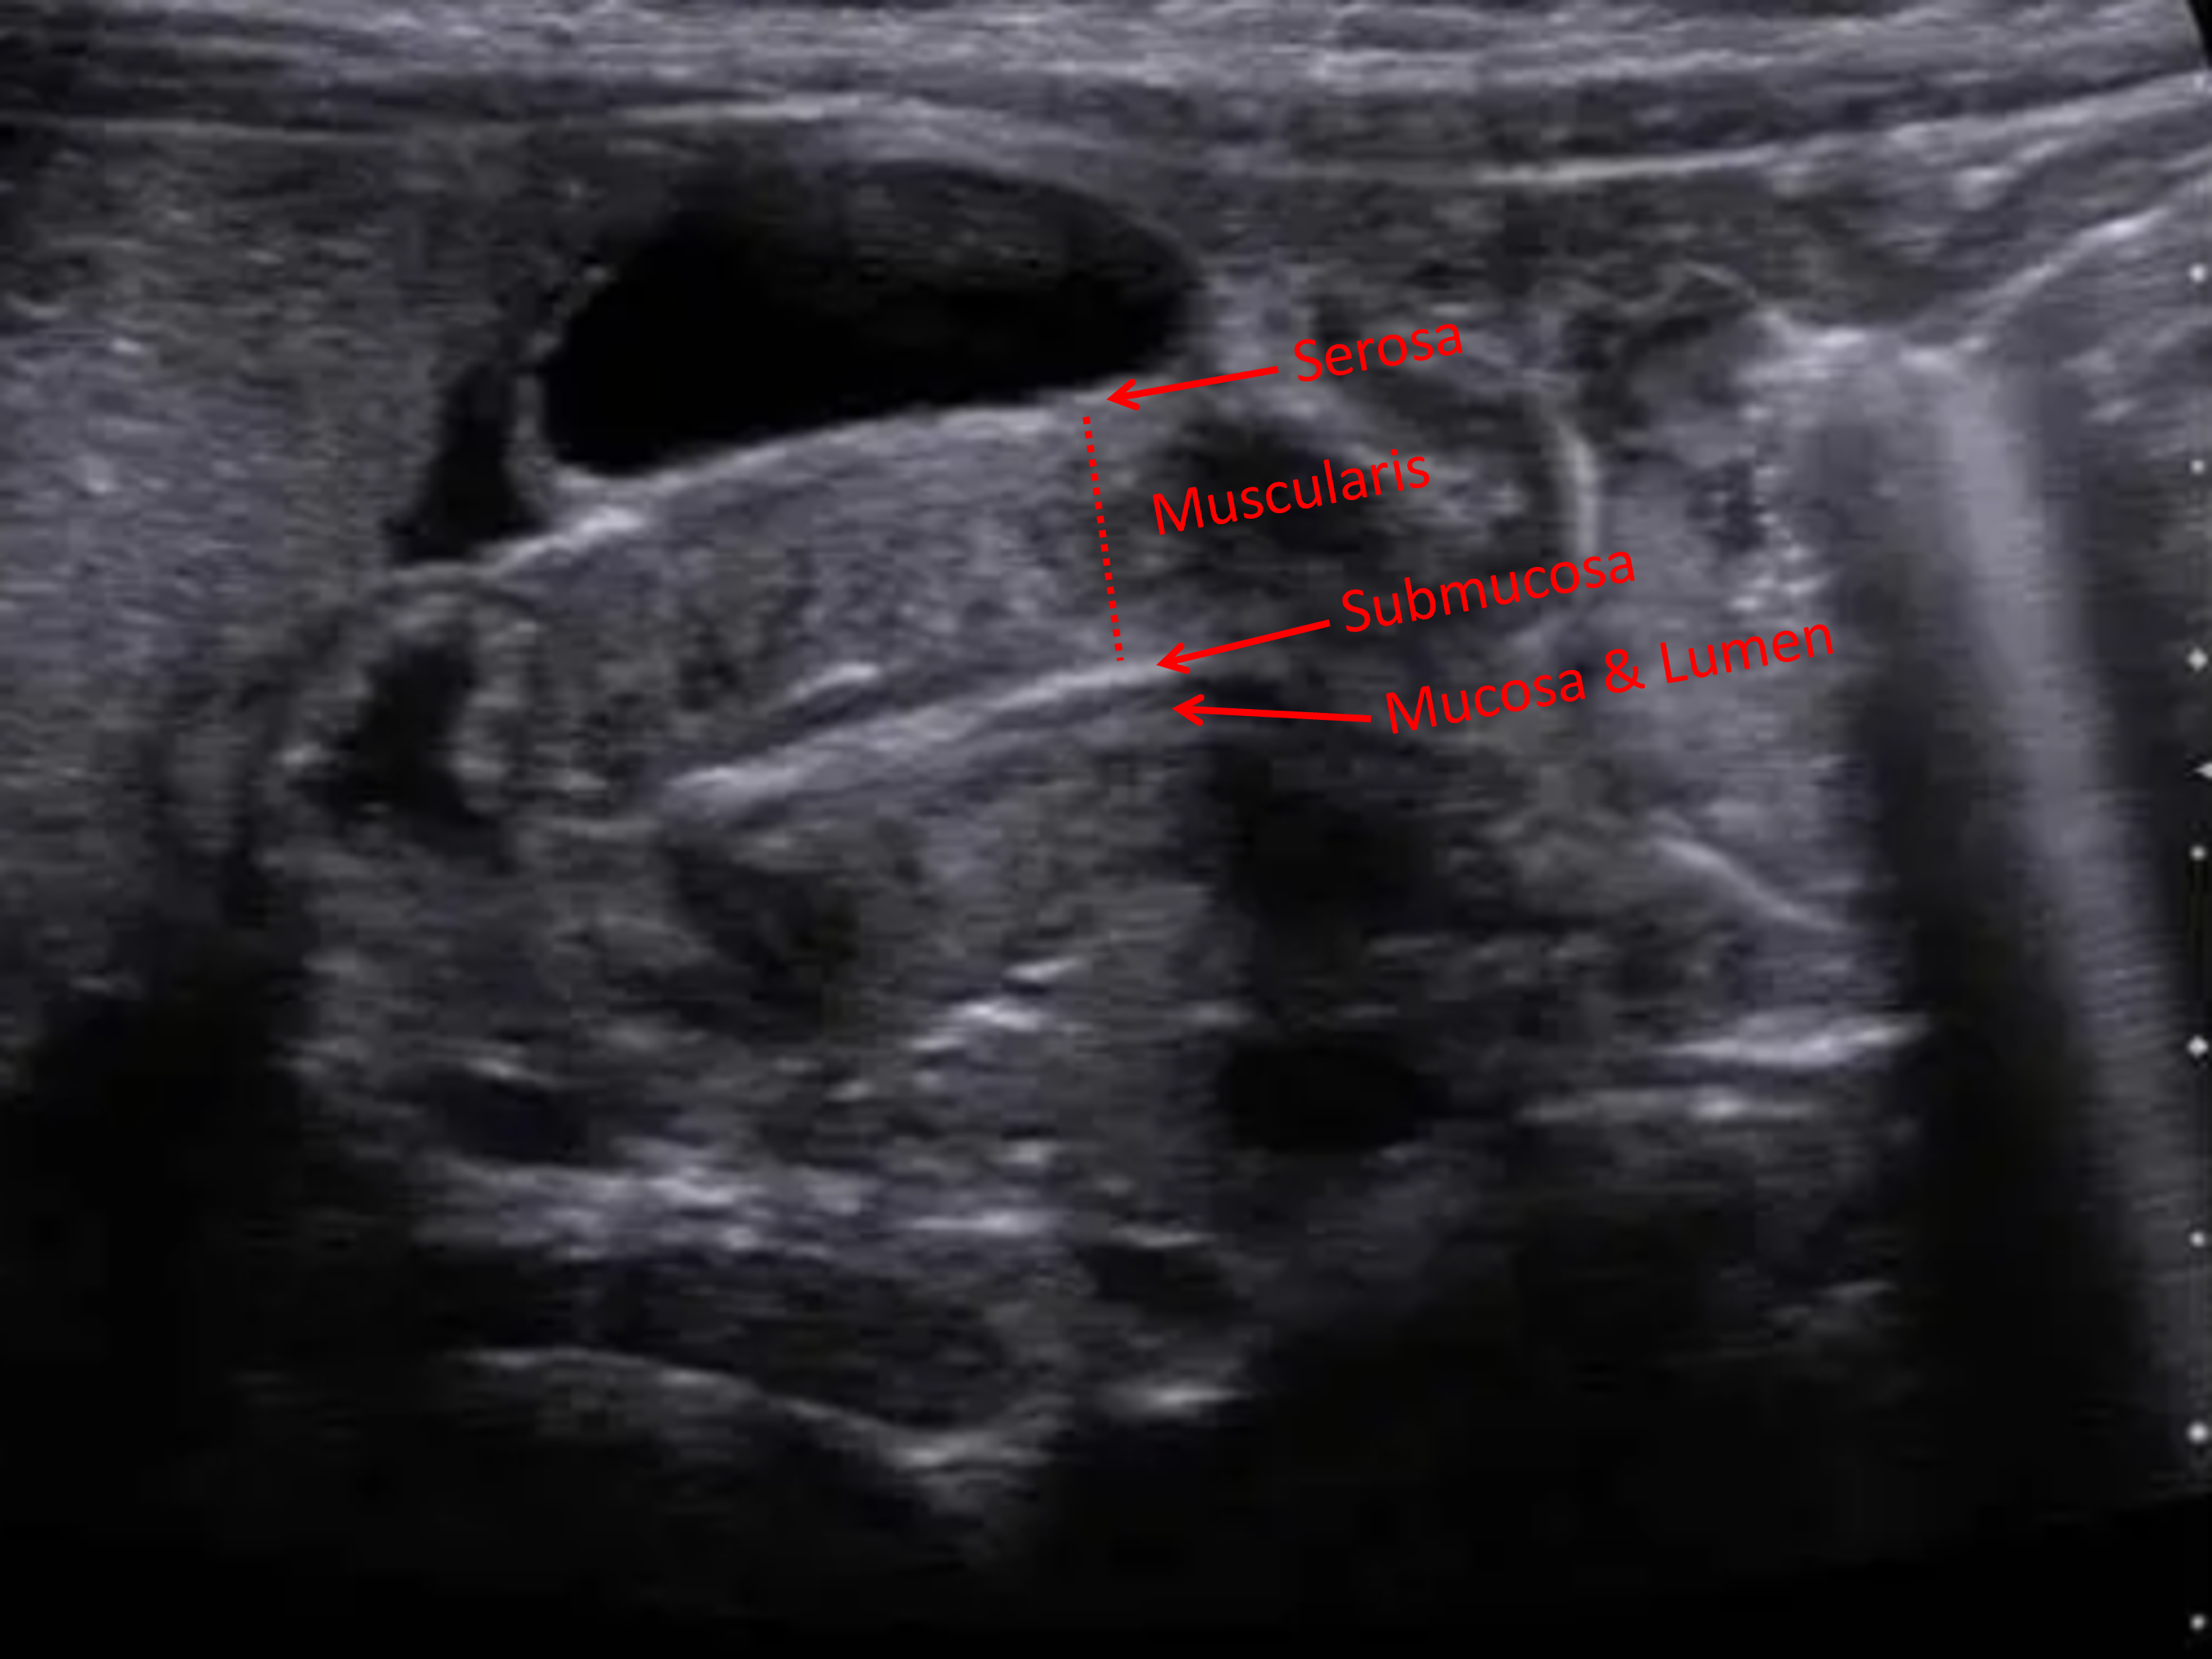

Age: 6 weeks (born at 40 weeks)

Sex: Male

Indication: Projectile vomiting

Hypertrophic pyloric stenosis

Sample ReportElongated pyloric channel with increased pyloric wall thickness and no observed bulk fluid transit from the stomach to the duodenum over 30 minutes of intermittent imaging. These findings are consistent with hypertrophic pyloric stenosis.